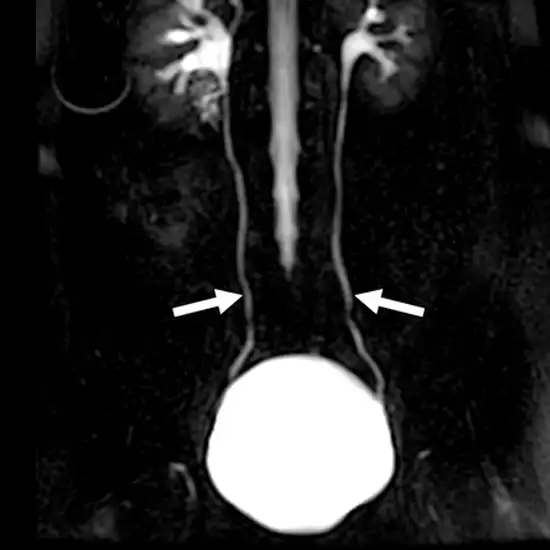

Magnetic resonance urography is a non-radiation imaging scan that uses only magnetic waves to capture images of the bladder, uterus, and kidney.

MRI urography is a magnetic resonance technique to produce non-radiation-based scan images of your urinary system including your bladder, kidney, and ureters. The MRI urography scan utilises magnets that are strong enough to produce a magnetic field. These magnetic fields are the basic principle on which the MRI urography scanner operates.

MRI urography scan is the diagnostic evaluation tool to find out abnormalities of the kidney and urinary system. The scan can help in the determination of renal malformations, identifications of ectopic ureters, hydronephrosis, etc. also in children having incontinence.